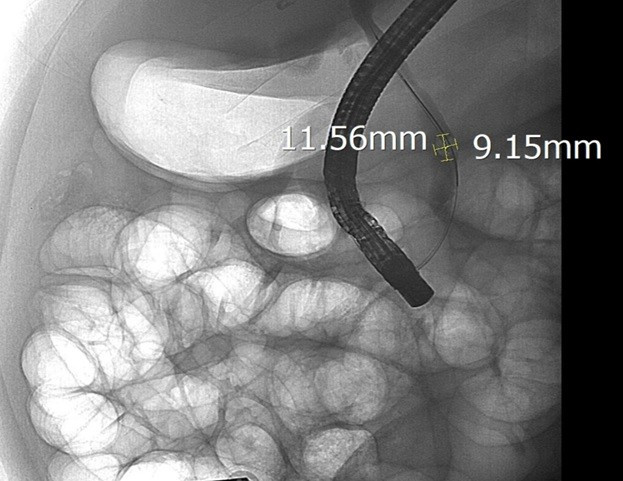

Sau khi hội chẩn, các bác sĩ Khoa Nội Tiêu hóa, Bệnh viện Hữu nghị đã chỉ định nội soi mật tụy ngược dòng (ERCP) dưới hướng dẫn của hệ thống chụp mạch số hóa xóa nền (DSA). Trong quá trình can thiệp, ê-kíp đã lấy thành công viên sỏi kích thước 11,5 x 9mm, giải phóng tình trạng tắc mật.

Sỏi ống mật chủ 'khủng' gây tắc mật nặng- Ảnh 2.

Hình ảnh sỏi ống mật chủ được lộ rõ dưới chụp DSA. Ảnh BVCC/Nguồn SKĐS